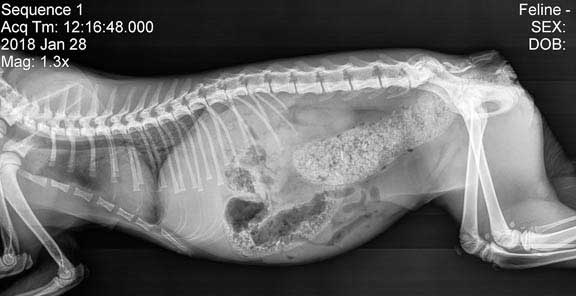

Radiologica Röntgentolk har utgått från chatt med din doktor som har en frågeställning som ska utredas. I detta exempel är det en katt som kan vara förstoppad. En komplett remiss har producerats. Remissens frågeställning tillsammans med röntgenbilder du kan ladda upp kommer att tolkas och generera ett remissvar.

Radiologica tar emot uppladdade röntgenbilder samt remissens frågeställning och gör en analys. Du laddar upp röntgenbilden och klickar på Tolka bilder.

I Stetoskåpet med Visuella Fynd (Röntgen) finner du ett strukturerat remiss-svar och rekommendationer. Din AI-doktor hanterar dessa resultat och återupptar chatten med dig. Du kan när som helst klicka på olika submenyer i Steoskåpet för hela statusen i ärendet.